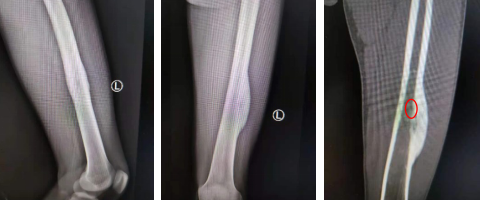

术前

随后,郑大伟主任组织团队讨论手术方案。郑主任指出,骨样骨瘤发病率较低,临床特点为夜间疼痛明显。肿瘤由瘤巢和周围硬化两部分组成,瘤巢呈圆形或椭圆形,直径多在0.1~1.5cm,由血供丰富的结缔组织、放射状骨样小梁、不同程度的钙化或骨化组成。本次手术的目标在于瘤巢的切除,从磁共振检查结果看,直径不到1cm的瘤巢藏匿于增生骨质内部,如何能准确定位瘤巢,是手术成功的关键步骤。可以考虑借助天玑骨科机器人的优势,“稳、准、快”地切除瘤巢。

手术当天,郑主任手术团队在3D扫描下完成对股骨病灶的三维影像建立,郑主任操作天玑骨科机器人,实现病灶的精确定位,凭借导航指引,微创、精准切除瘤巢。经测量,瘤巢大小约0.8cm× 0.5cm。肿瘤切除后患者原有的疼痛症状消失。

术中定位肿瘤瘤巢